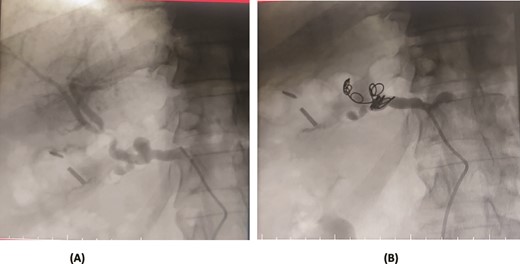

A 56-year-old female underwent a pancreaticoduodenectomy (PD) for pancreatic head adenocarcinoma. On the 6th postoperative day, she presented with nausea and vomiting. A contrast-enhanced CT scan revealed the presence of a pseudoaneurysm originating from the common hepatic artery. Angioembolization was promptly performed to control the bleeding. The procedure was successful, and the patient recovered well postoperatively. At follow-up, the patient was doing fine with no further complications (Fig. 2).

Case 2. (A) CT angiogram showing pseudoaneurysm CHA. (B) Angioembolization of CHA with gel foam